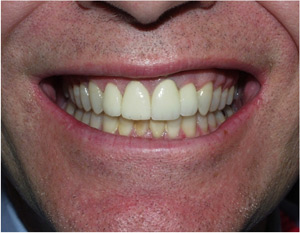

Crowns are a type of dental restoration which, when cemented into place, fully cover the portion of a tooth that lies at and above the gum line. In comparison, fillings are dental restorations that fill in or cover over just a portion of a tooth. Since dental crowns encase the entire visible aspect of a tooth, a dental crown in effect becomes the tooth's new outer surface. Crowns can be made out of porcelain, metal (gold or other metal alloy), or a combination of both.

- Restorations will look like your natural teeth

- Can improve the cosmetic appearance of a tooth

Since a dental crown will encase the visible portion of a decayed tooth, any dental crown that has a porcelain surface can be used as a means to improve the cosmetic appearance of a tooth. However, dental crowns are best utilized as a way to improve the cosmetic appearance of a tooth when the crown also simultaneously serves other purposes, such as restoring a tooth to its original shape or strengthening a tooth.